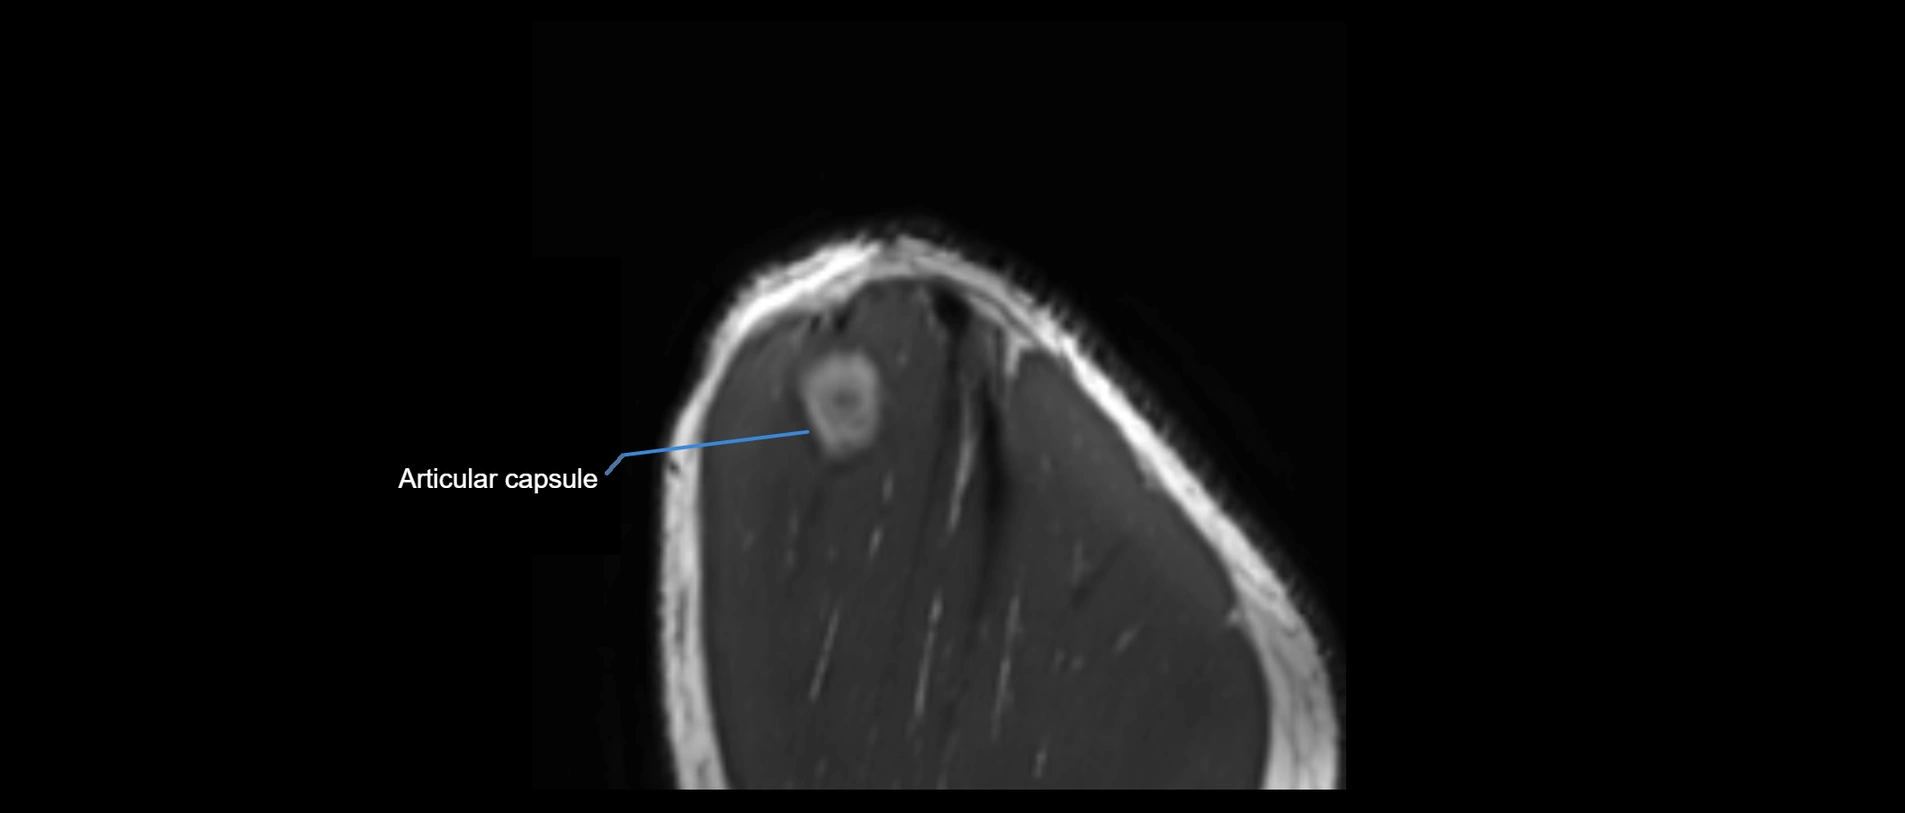

MRI images

image